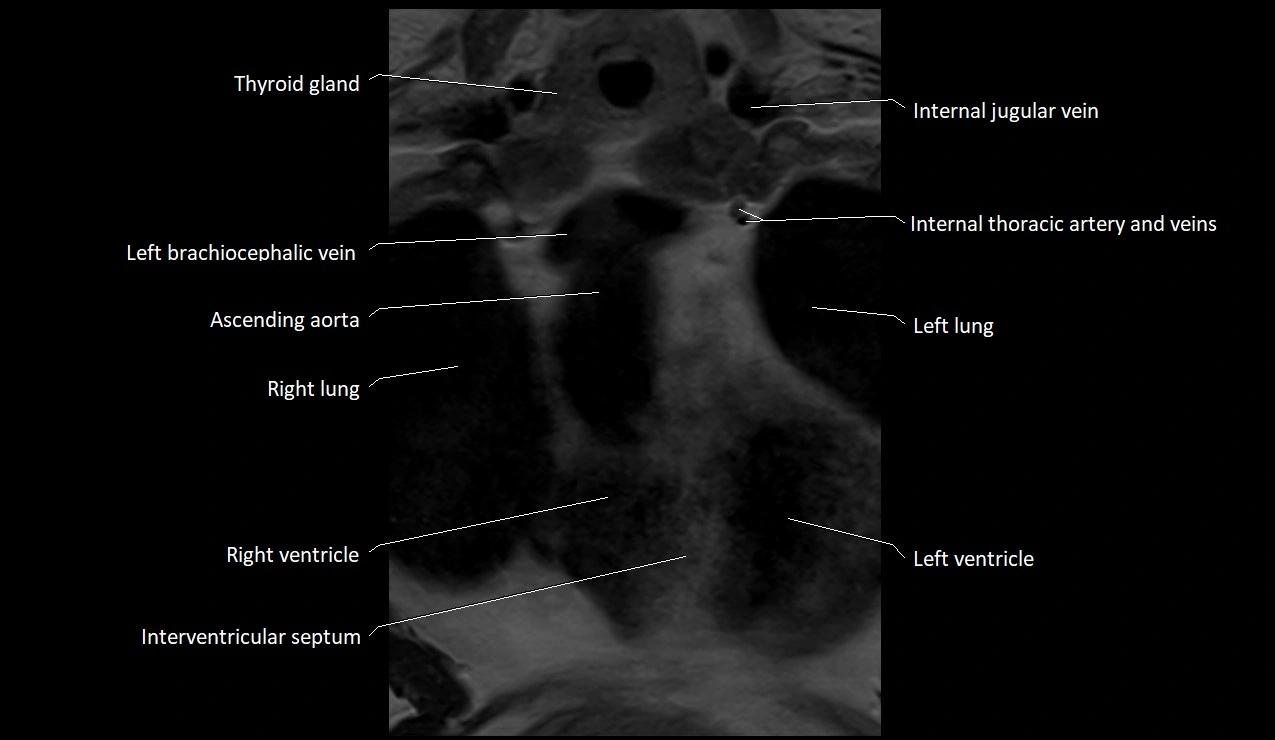

MRI images

image